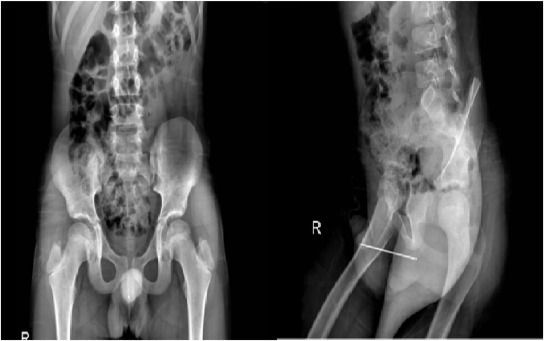

▲伊朗一名10歲男童把長8.7公分的縫針插進生殖器,此個案被發表在《泌尿科病例報告》(Urology Case Reports)期刊。(圖/翻攝自泌尿科病例報告期刊)

每日郵報報導,這名10歲男童不知何種原因把縫針插進尿道後卡住,期間儘管有正常排尿一次,但縫針仍卡在尿道中。依據X光影像,針的所在位置使得院方難以使用傳統手法來解決,也就是把異物推至生殖器尖端取出。